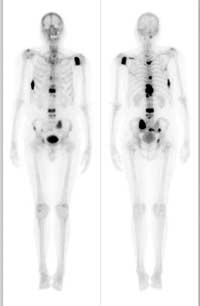

روش های عکس برداری می توانند به تعیین محل و اندازه ی تومورهای استخوان و گسترش یا عدم گسترش آن ها به سایر نقاط بدن کمک کنند. در این مقاله با علائم سرطان مغز استخوان و نیز روش های درمان آن آشنا می شوید. یک تومور رشد غیر طبیعی بافت در بدن است. سلول های توموری توانایی تنظیم کردن ندارند بنابراین سلول های بیشتری تولید می کنند و منجر به تشکیل یک توده می شوند در حالی که بسیاری از تومورها سرطانی.

تشخیص سرطان استخوان. استئوسارکوم شایع ترین نوع است که بیشتر بر کودکان و نوجوانان زیر 20 سال تأثیر می گذارد. جراحی اغلب اولین انتخاب درمانی می باشد اگرچه گاهی اوقات قطع کردن عضو لازم می باشد. درمان سرطان استخوان به نوع سرطان بستگی دارد.